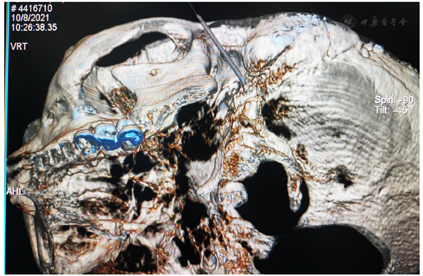

鉴于MS与HFS的临床表现有高度相似之处,我们设想,用于治疗HFS的面神经射频技术有望用治疗MS。经报请医院伦理委员会讨论通过(LS2019-013),决定给患者施行双侧面神经射频治疗。术前向患者及其家属详细交待操作经过和可能出现的轻度面神经麻痹并发症,取得知情同意并签署书面知情同意书后,嘱患者右侧向上侧卧于CT台上,安置血压、心电图、脉搏血氧饱和度监测设施并给予鼻导管吸氧,并在耳垂前后放置CT定位定位栅(图2)。用鼻旁窦模式拍摄头颅定位像,并对乳突区进行层厚3 mm轴位扫描,选取含茎乳孔且无颞骨鼓部骨质阻挡的CT层面作为穿刺层面,并在该层面上设计穿刺路径:以右侧茎乳孔为穿刺靶点,用CT自带测量工具软件由右茎乳孔向前上拉直线,该线与皮肤的交点即为穿刺点,测量穿刺深度(穿刺点至靶点的距离)和穿刺角度(穿刺路线与矢状面的夹角)(图3)。对穿刺点进行局部麻醉,用长度为10 cm、裸露端为5 mm的7号射频针在CT引导下穿刺至靶点(图4)并CT扫描三维重建观察确认(图5),随后用低频(2 Hz)电流进行运动神经刺激测试,0.5 mA电流电刺激即能诱发出右侧面肌出现与电刺激相同频率痉挛性抽动,见视频,给予65℃标准射频消融,同时嘱患者鼓腮、闭眼,射频第27秒鼓腮漏气,右眼不能紧闭,即停止射频,结束手术,见视频。2 d后同样于CT引导下行左侧茎乳孔穿刺面神经射频消融治疗(图6,图7,图8)。